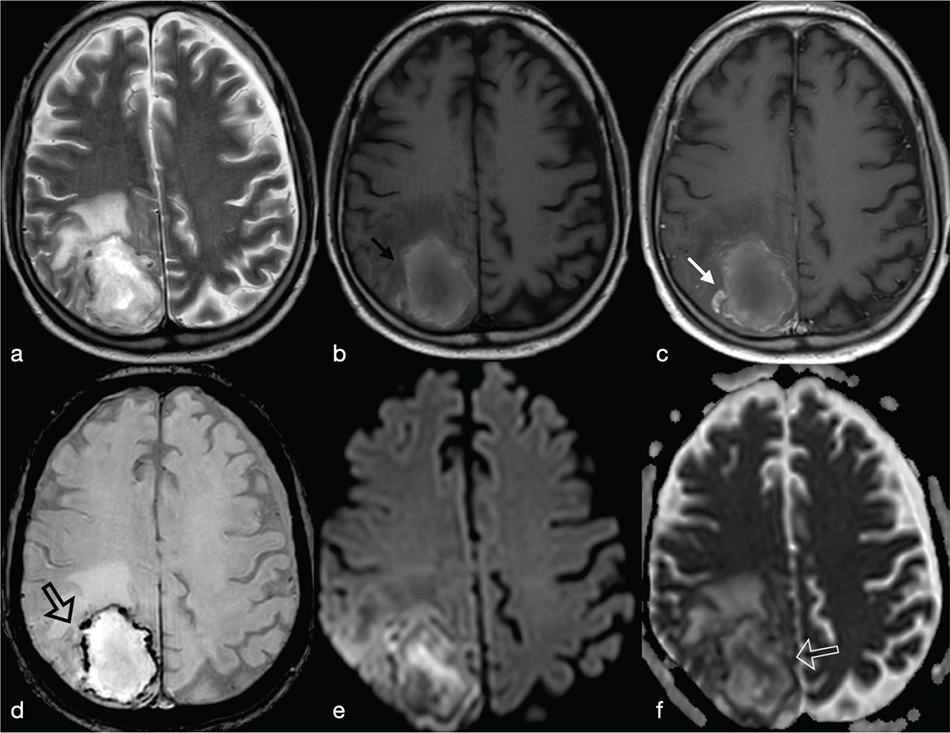

These include high-grade gliomas (WHO grade IV) and metastases. They usually exhibit a T2w hypointense, irregular or incomplete, capsular rim.8 After injection of Gd, gliomas show non-homogeneous enhancement with some nodular areas (Figure 13). Metastases, on the other hand, can exhibit an enhancement pattern similar to pyogenic abscesses. However cystic neoplasms, often have a thicker medial margin if compared with pyogenic BA (Figure 6).9 Peripheral dark signals on SWI can be also found in glioblastomas and are related to the neoplastic intralesional neoangiogenesis and haemorrhage.8 As a rule, necrotic brain tumours have high ADC values. However low ADC values have been described in hyper-cellular tumour such as metastases from lung, breast, colorectal and testicular cancer (Figure 11).5 Moreover, necrotic tumours usually show an increase of neoangiogenesis with higher values of rCBV than abscesses in the periphery of the lesion.

FIG 13. Necrotic Tumour in a 38-Year-Old Man: (a-c) a Left Temporal Lobe Cystic Mass is Shown. On T1w+Gd (c), the lesion shows irregular rim-enhancement. The central part of the lesion shows increased diffusivity (d, e) consistent with intratumoural necrotic degeneration. The rCBV map (f) showed increased perfusion within the enhancing rim of the lesion (open arrow). Final diagnosis was glioblastoma.